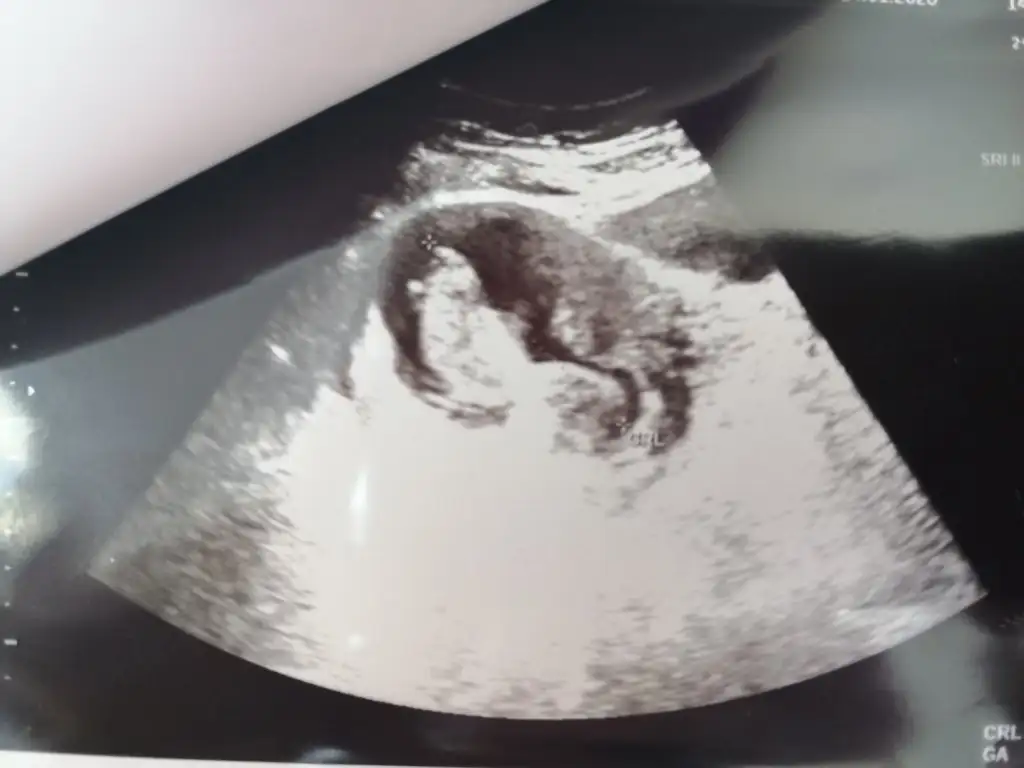

Erkek gibi ama nubun birazını dr + getirmiş emin olamadım başka usg varsa paylaşın

12+2 bana da yorum yaparmısınız, doğru gönderebildim mi bilemiyorumDr + tam nuba denk getirmiş başka usg varmı![]()

12+2 günlük, bana da yorum yapabilir misiniz

Kız gibi